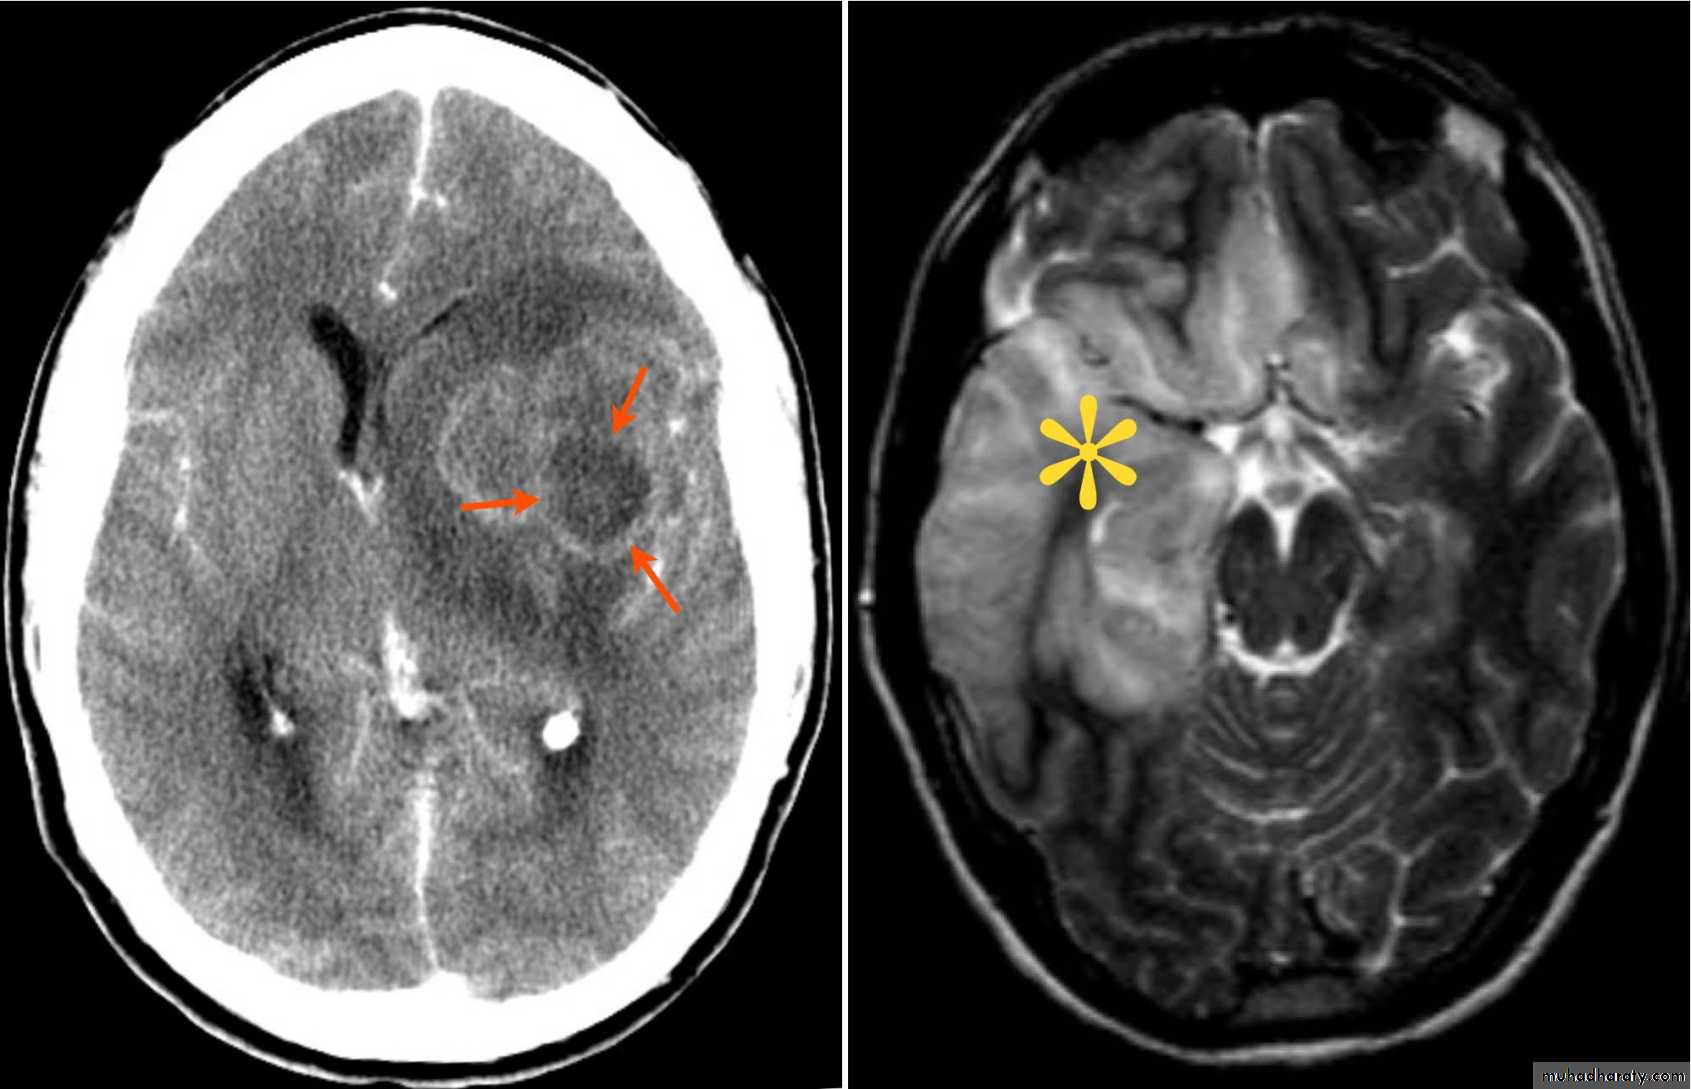

C-Intracranial hemmorhage (I.C.H.)

I.C.H.